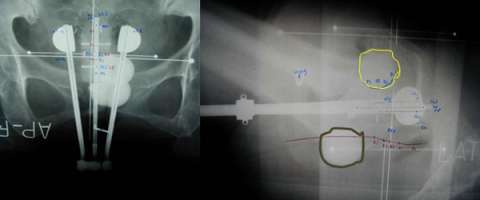

In the images below for example on the right is an anterior-posterior view of a vaginal applicator inserted in the vagina. You can see the cylinder pushing up against the top of the vaginal apex. You can't see the outline of the entire bladder and rectum but one way to approximate them is to place foley catheters in the bladder (yellow outline) and the rectum (brown outline) so they can be visualized.

An alternative to this is to use CT compatible applicators and to use CT imaging. The advantage of this is that CT imaging allows you to see the anatomy in more detail than on X-rays. For example, a CT image with a vaginal applicator in place looks like the following:

One can actually "see" the anatomy including the bladder (yellow) and rectum (brown). The cylinder is outlined in red. By being able to clearly see things we can more effectively optimize the radiation dose to the target and limit the dose to normal tissues.